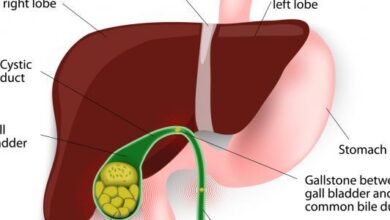

- الكشف عن البيليروبين: فوجود البيليروبين (بالإنجليزية: Bilirubin) في البول قد يدل على تعرض الكبد للتلف أو إصابته بأحد الأمراض والمشاكل الصحية.

- الكشف عن الدم: والذي قد يكون دلالة على تعرّض الكلى للتلف، أو إصابتها بالعدوى، أو وجود ورم سرطاني أو حصى في الكلى أو المثانة.